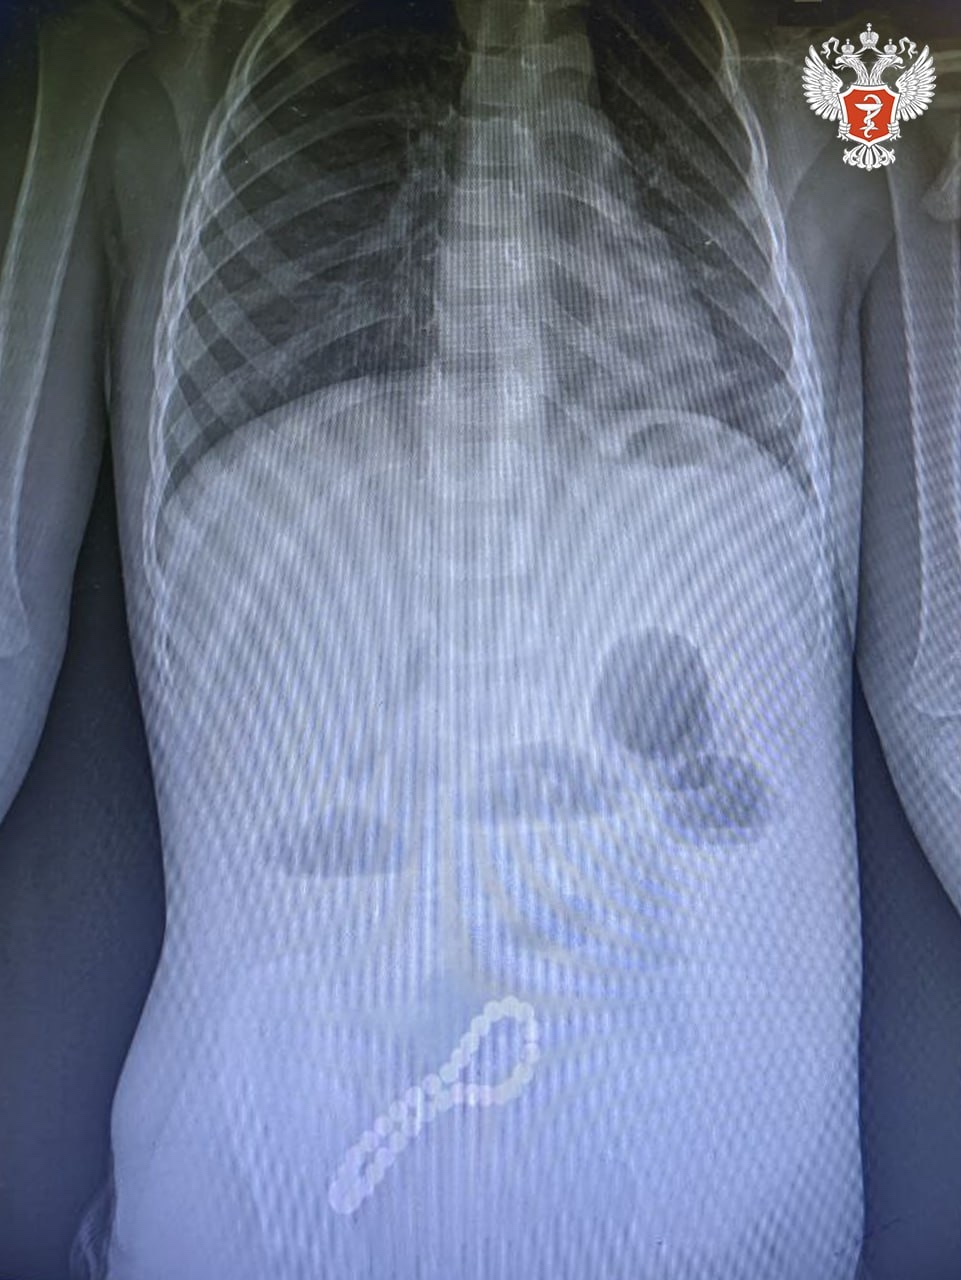

➡️ Хирурги выявили нарушение функций работы кишечника. При помощи рентгенограммы врачи поставили диагноз — инородное тело в кишечнике и приняли решение о его удалении.

— Было принято решение об операции. Мы провели минилапаротомию и увидели, что магнитами, которые притянулись друг к другу, соединены петли кишки в ее стенке отверстия. В ходе операции удалили все 30 магнитных бусин: 29 маленьких и одну большую. Сейчас ребенок поправился. Его жизни и здоровью ничего не угрожает, — рассказал главный внештатный хирург Минздрава Рязанской области Олег Ларькин.